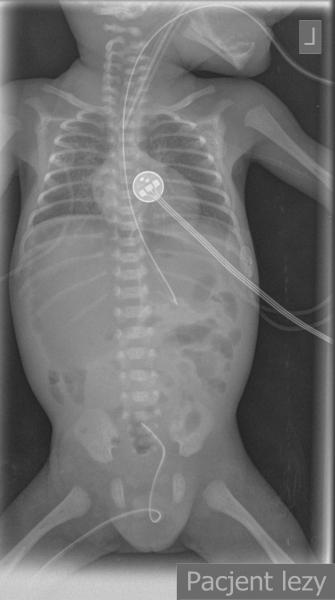

Noworodek w 7-ej dobie życia z podejrzeniem perforacji przewodu pokarmowego.

Przypadek 9: Noworodek w 7-ej dobie życia (wcześniak urodzony w 26 Hbd) z podejrzeniem perforacji przewodu pokarmowego.

Rozpoznanie: Na zdjęciach przeglądowych klatki piersiowej i jamy brzusznej (a-p w pozycji leżącej i boczne poziomym promieniem) uwidoczniono wolny gaz (strzałka) pod przednią ścianą jamy brzusznej - perforacja przewodu pokarmowego.

Pytanie: Jakie są cechy perforacji przewodu pokarmowego na zdjęciach rtg? Czy można rozpoznać obecność wolnego powietrza w jamie brzusznej na zdjęciu a-p wykonanym w pozycji leżącej (np u małych dzieci lub pacjentów w OIOM) ?